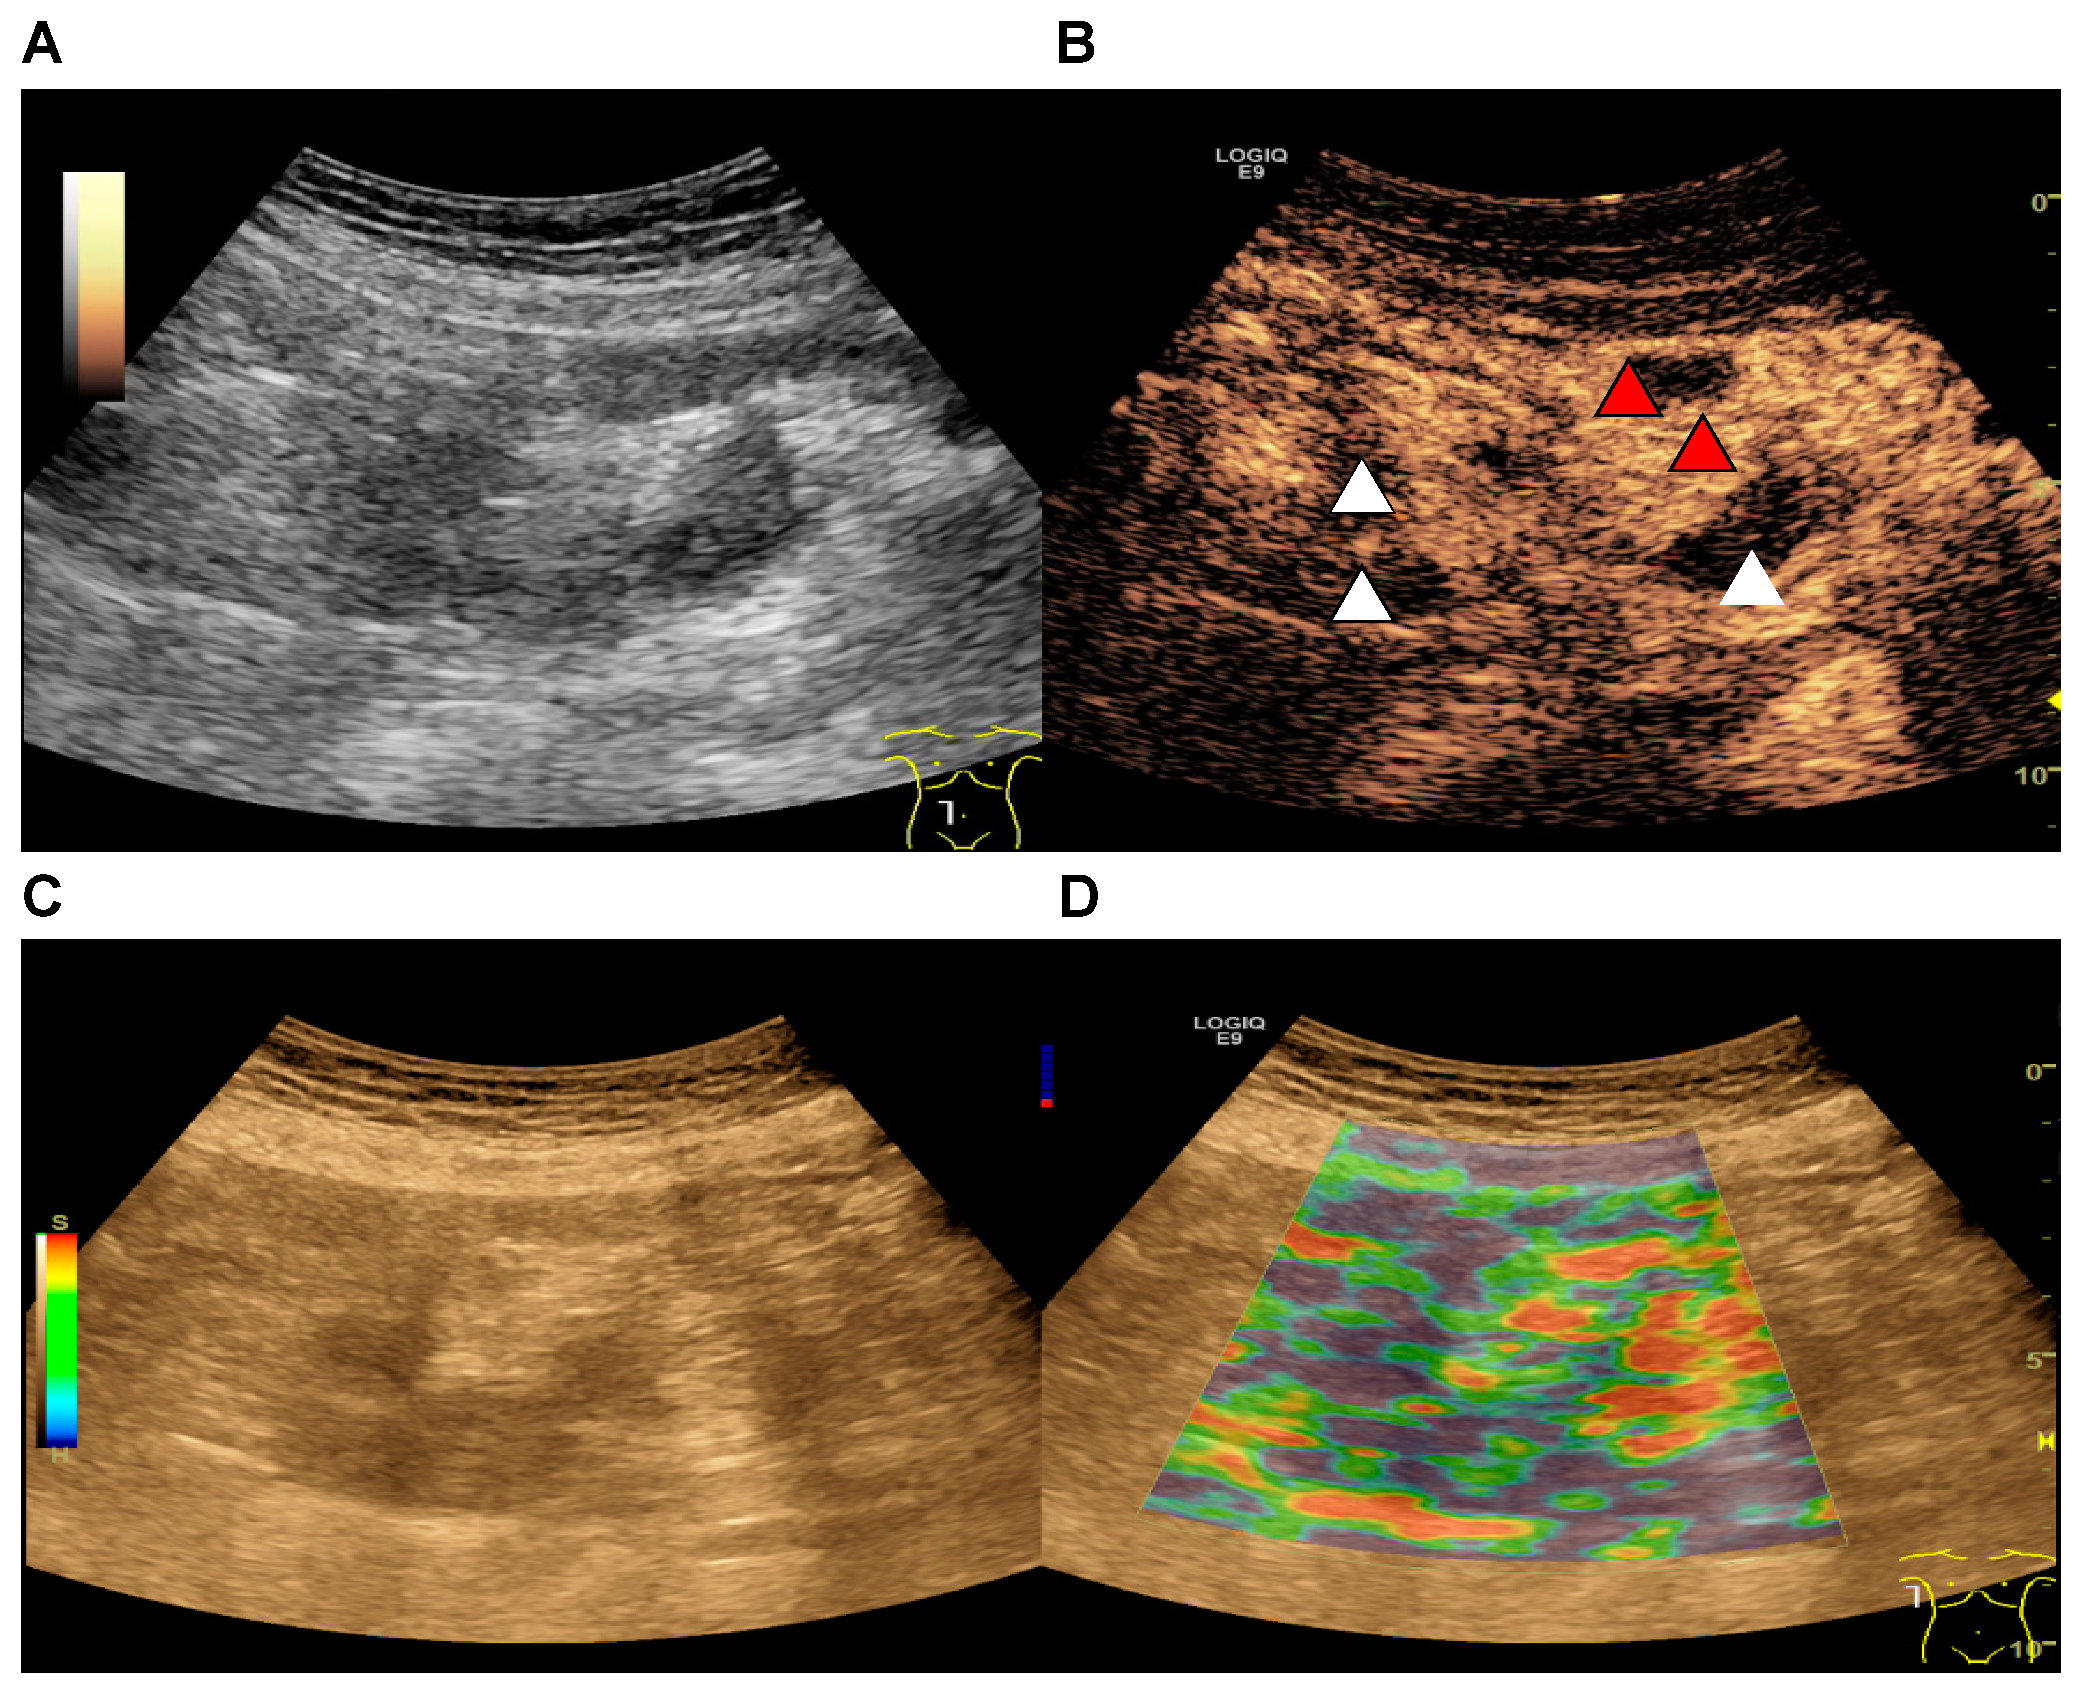

2.2. Ultrasound Examination

2.3. Strain Elastography

2.4. CEUS

2.5. Parametric Analysis